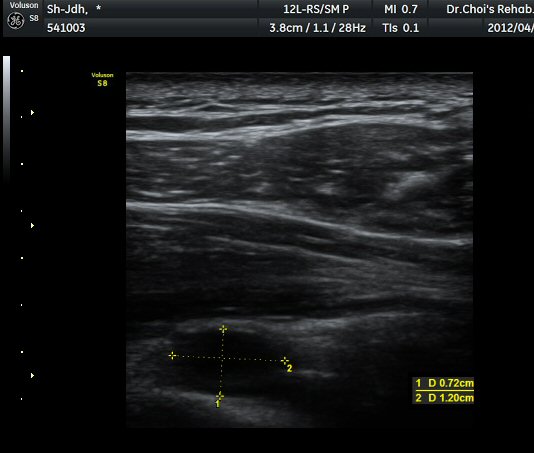

¾î±ú µÚ °üÀý¼ø °Ë»ç¿¡¼­ °üÀý¼ø Ç¥Ãþ¿¡ Àú¿¡ÄÚ ¼ö¾×Àú·ù°¡ °üÂûµÊ(»çÁø 4).

ŽÃËÀÚ¸¦ Á» ´õ µÚ·Î À̵¿ÇÏÀÚ °üÀý¼ø ³»Ãø °¡½Ã°üÀý¿À¸ñÆÐÀÓ(spinoglenoid notch)¿¡

¿øÇü¸ð¾çÀÇ Àú¿¡ÄÚ ³¶Á¾ÀÌ °üÂûµÊ(»çÁø 5, 6).

ÃÊÀ½ÆÄ °Ë»ç ; ³¶Á¾ÀÇ Å©±â°¡ Å©°Ô(1/5) ÁÙ¾îµë

ÈíÀÎ Àü ³¶Á¾ÀÇ Å©±â